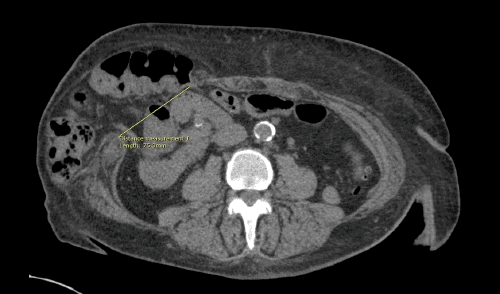

On postoperative day (POD) 4 following transplantation, she developed a palpable bulge at her incision site, concerning for fascial dehiscence, which was confirmed on computed tomography (CT) (Figure 1A). She was taken to the operating room (OR) for repair. Intraoperatively, the fascia was noted to be thin and friable, making primary approximation difficult. A Permacol™ biologic inlay mesh was utilized to bridge the fascial defect and was secured circumferentially to the fascial edges with interrupted Prolene sutures; the peritoneal cavity was not entered during this second operation. Despite this, on POD 2 following this mesh repair (POD 6 from initial transplant), the patient acutely re-developed a palpable bulge, again concerning for recurrent fascial dehiscence. She returned urgently to the OR, where the fascial edges were found to be ischemic and retracted from the previously placed mesh, resulting in a repeat dehiscence (Figure 1B). Given her immunosuppressed state, pre-existing obesity, and the already failed attempt at mesh closure, the decision was made to explant the mesh, débride non-viable fascia, and perform a tension-free closure of only the overlying subcutaneous tissues and skin, effectively creating a planned ventral hernia. The peritoneal cavity was not violated during this third operation. After a prolonged hospitalization, the patient recovered appropriately and was discharged home.

Figure 1. CT Demonstrating Sequential Fascial Dehiscences. Published with Permission

Axial CT images. (A) Scan obtained on POD 2 following kidney transplantation, demonstrating the initial fascial dehiscence with herniation of intra-abdominal contents. (B) Scan obtained on POD 7 following kidney transplantation (and after the first attempted mesh repair), showing recurrence of the fascial dehiscence with evidence of fascial edge retraction from the biologic mesh